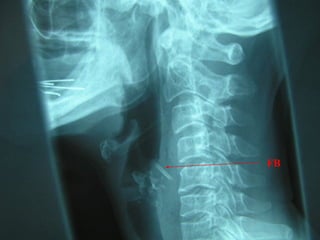

FB Throat - Investigations

Lateral neck XR

CXR

Barium swallow

CT scan – without contrast

Rigid oesophagoscopy

FB

Osteophyte